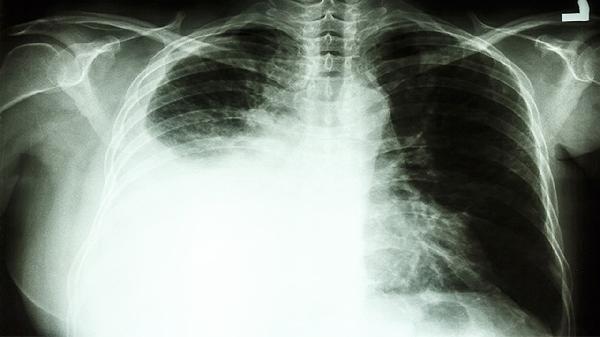

肺上有8毫米结节是怎么回事

肺部发现8毫米结节多数为良性病变,可能由感染性肉芽肿、陈旧性瘢痕、错构瘤、早期炎症或粉尘沉积等因素引起。临床建议定期随访观察,必要时需结合病理检查明确性质。

发现肺结节后应避免焦虑,8毫米结节恶性概率不足5%。建议保持规律作息,每日保证30分钟有氧运动如快走、游泳,增强肺功能。饮食注意增加十字花科蔬菜和富含维生素C的水果摄入,限制加工肉类。严格戒烟并减少厨房油烟暴露,使用空气净化器改善室内空气质量。职业暴露人群需做好防护措施,每3-6个月复查低剂量CT,若结节增长超过2毫米或出现分叶、毛刺等特征应及时胸外科就诊。